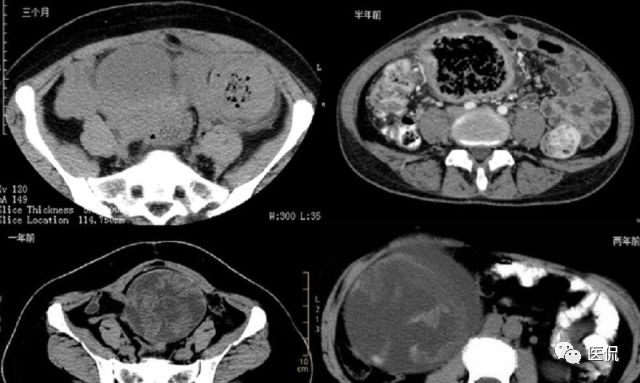

腹腔内残留的纱布在人体内引起渗出或液化坏死并纤维包裹形成异物性脓肿(纱布瘤)。纱布瘤的影像特点:圆形或卵圆形肿块,较大,有完整包膜,薄壁,较少的情况下为厚壁,边界较完整,增强后薄膜可以持续强化。不同时期的纱布瘤可以有不同表现:早期(10个月或半年内)多表现为蜂窝状;2~5年内一般表现为囊性飘带状;10~20年之后则为实性软组织密度,包膜钙化呈钙化网状结构。手术过程中残留在人体内的医用纱布所形成的肿瘤样病变。

相关病例补充

手术所见:腹腔内无腹水,肿块位于右上腹,约15x10x8cm大小 ,周围网膜包裹粘连,向胆囊三角处延续,呈囊性,与周围结构无明显浸润,仔细分离粘连,逐步游离暴露肿块,见肿块与右肾及结肠、十二指肠无明显关系,初步确定为肿大的胆囊,继续向肝门部游离,见肿块与胃窦粘连,因分离困难,决定切开肿块。穿刺肿块有黄色脓液抽出,考虑胆囊脓肿,切开囊壁,吸出大量黄色混浊脓液约1200ml,探查囊腔,见粘膜层为胆囊粘膜,腔内有一异物残留,经证实为医用盐水纱布,取出纱布约15x15cm大小,封存。继续游离胆囊至完整切除,检查囊壁无明显占位病变。

病理诊断:胆囊异物残留,胆囊化脓性炎、胆囊脓肿。